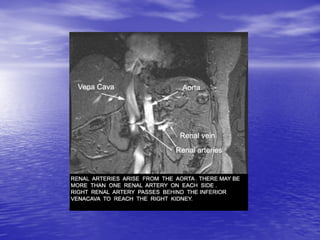

HỆ THỐNG MẠCH MÁU

CHI PHỐI THẬN

- Động mạch thận (P)	xuất phát từ hướng

trước bên (10	giờ),	động mạch thận (T)	xuất

phát từ hướng sau bên (4	giờ),	ngay dưới vị

trí xuất phát của động mạch mạc treo tràng

trên 1	cm

- Thân động mạch thận chạy ra sau và hướng

về rốn thận

Động mạch thận (P)

khảo sát từ hướng cắt

chếch (bệnh nhân nằm

chếch phải – sau)	lấy

gan làm cửa sổ xuyên

âm

- Động mạch thận

(P)	khảo sát từ

hướng cắt chếch

(bệnh nhân nằm

chếch trái – sau)

- Để đầu dò theo

hướng cắt vành

động mạch chủ

bụng thì sẽ nhận

được hình hai

động mạch thận

cùng một lúc

- Các tĩnh mạch được khảo sát từ cùng hướng của động mạch

cùng tên,	thường có khẩu kính lớn hơn động mạch và chạy phía

trước động mạch thận cùng tên.

- Tĩnh mạch thận (T)	trước khi đổ vào tĩnh mạch chủ dưới thì

chui ngang qua	“gọng kìm”	động mạch mạc treo tràng trên và

động mạch chủ bụng thì khẩu kính có giãn lớn hơn